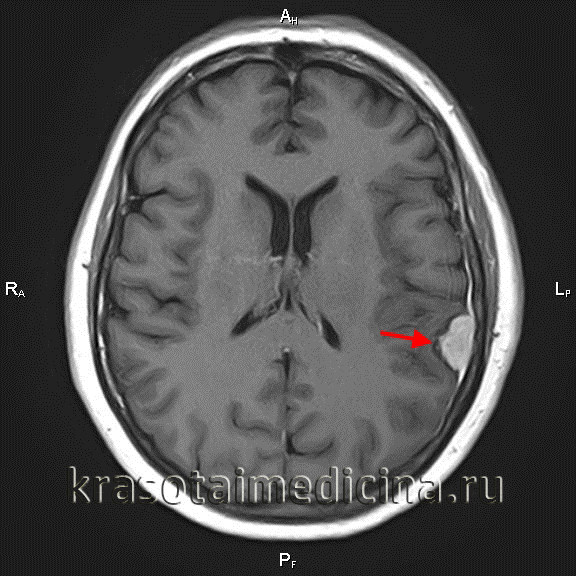

МРТ головного мозга (С+). Объемное образование в теменной области слева, широким основанием прилежащее к мягкой оболочке

КТ головного мозга позволяет выявить опухоль, но в основном применяется для определения задействования костной ткани и опухолевых кальцинатов. Позитронно-эмиссионная томография (ПЭТ головного мозга) применяется с целью определения рецидивирования менингиомы. Окончательный диагноз выставляется неврологом или нейрохирургом, исходя из результатов гистологического исследования биоптата, которое определяет морфологический тип опухоли.